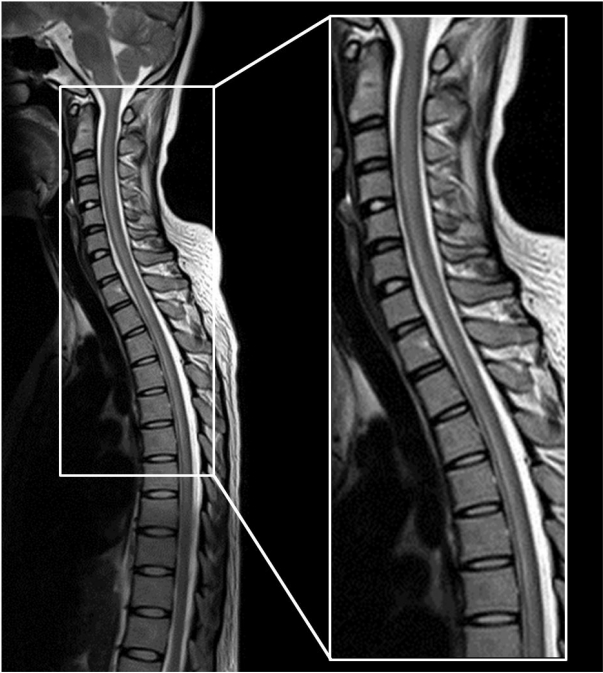

27세 여자가 3일 전부터 시작된 두통 및 발열을 주소로 입원하였다(Fig. 1). 특별한 기저질환은 없었으며, 최근 선행된 호흡기감염의 징후도 없었다. 방문 당시 39℃로 고열이 있었던 점 외에 다른 활력징후는 정상이었다. 내원 당시 촬영한 뇌 전산화단층촬영에서 특이소견은 없었고, 신경학적 진찰에서 의식은 명료하였으나 경부강직이 관찰되어 뇌수막염 의심하에 뇌척수액검사를 하였다. 뇌척수액은 투명하였고, 뇌척수액 압력은 280 mmH2O로 높았으며, 백혈구 120/mm3 (림프구 90%), 단백질 135 mg/dL, 포도당 53 mg/dL (혈청포도당 100 mg/dL)였다. 뇌척수액의 항산균염색은 정상이었고, 균은 배양되지 않았으며, 바이러스 및 결핵균 중합효소연쇄반응검사도 음성이었다. 혈액검사를 통한 항체검사에서 거대세포바이러스, 엡스타인-바바이러스, 단순헤르페스바이러스, 수두포진바이러스에서는 모두 음성이었으나, 입원 4일째 효소면역법(enzymelinked immuno-sorbent assay)검사로 시행한 Mycoplasma에 대한 혈청 immunoglobulin G (IgG)와 IgM 항체 역가가 각각 1:74, 1:3으로 증가된 것을 확인하였다. 이에 azithromycin (zithromax 500 mg)으로 경험적 항생제 치료를 시작하였다. 입원 8일째(azithromycin 투여 4일째), 갑자기 기면(drowsy)과 혼돈(confusion)을 보이고 왼쪽 눈에서 더 심한 양안의 외측 주시마비를 보였다. 이에 시행한 뇌자기공명영상에서 양측 측두엽 피질의 부종이 관찰되었다(Fig. 2). 뇌척수액 추적검사를 시행하였고, 뇌척수액 압력은 200 mmH2O로 감소되었으며 백혈구는 변화가 없었으나 단백질은 220 mg/dL로 상승되었다. 복시가 두개내압 상승으로 인해 유발되었을 가능성을 고려하여 뇌압 및 부종 조절을 목적으로 dexamethasone을 5일간 투여하였고, 혈청검사상 특정 바이러스가 검출되지는 않았으나 임상적으로 바이러스뇌염 가능성이 의심되어 acyclovir를 추가하여 투여하기 시작하였다. 입원 11일째(dexamethasone을 투여한 지 3일째) 의식이 명료해지고 혼돈상태도 호전을 보였다. 입원 18일째, 두통은 남아 있었으나 복시 및 의식혼돈은 모두 호전된 상태로, 연고지의 2차 병원으로 퇴원하였다. 하지만 퇴원 4일 만에 전신강직간대발작을 한 차례 한 후 다시 본원 응급실로 전원되었다. 재입원한 지 3일째 갑자기 양 하지의 근력저하(Medical Research Council grade 2)를 보였고, 배뇨장애가 발생하여 도뇨관을 삽입하였다. 이에 시행한 척추 자기공명영상(whole spine magnetic resonance imaging)에서 척수 전체에 T2 강조 영상에서 신호증강이 관찰되었다(Fig. 3). 영상의학소견과 임상양상으로 횡단성척수염을 의심하여 부신피질호르몬제 15 mg/kg을 5일간 정맥 주사하였으나, 증상의 호전이 없어 60 mg을 경구 투여하면서 면역글로불린 정맥 주사(intravenous immunoglobulin, IVIG)를 시작하여 5일간 유지하였다. IVIG 투여 3일째부터 양 하지의 근위부의 근력 호전을 보이기 시작하였고, 재활 치료를 병행하면서 더욱 호전되어 증상 발생 50일째 걷기가 가능할 정도가 되었으나, 배뇨장애는 호전되지 않아 도뇨관을 유치한 상태로 퇴원하였다. 회복기에 추적검사한 Mycoplasma 혈청 IgG 역가는 1:100 이상으로 상승되었고, IgM 항체 역가는 1:1.4로 감소를 보였다. 10개월이 경과한 후에는 자가 배뇨가 가능하지만 절박 요실금이 남아 있는 상태이다.

신경학적 합병증과 관련된 예후인자 중 좋은 예후인자는 선행감염이 있고, 일주일 이내 호전의 시작을 보이는 경우, 10세 미만, 허리엉치 척수부위에 병변이 있는 경우이고, 나쁜 예후인자로는 시작부터 이완된 하지(flaccid leg)가 있거나, 괄약근기능까지 침범한 경우, 증상 발생부터 24시간 이내 급격한 증상 진행을 보이는 경우이다[10]. 본 환자는 성인 여성으로 선행감염이 없고, 증상 발생 첫날부터 20일 동안 다양한 증상이 지속적으로 나타났으며, 경추 부위부터 길게 보이는 척수 병변과, 배뇨장애 그리고 양 하지 위약감이 발생 24시간 이내 급격히 진행하였다는 점에서 예후가 좋지 않을 것을 예상할 수 있었다. 환자는 증상 발생 2달째부터 보행은 가능하였으나 1년이 경과한 현재에도 배뇨장애는 여전히 남아있는 상태이며 지속적으로 재활 치료 중에 있다.